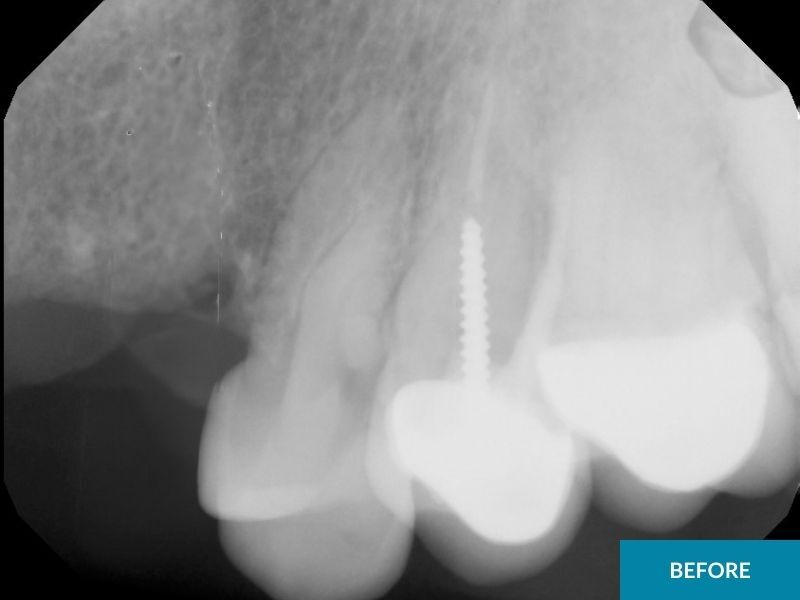

Placing dental implants and then putting a cap on it is a great way to replace a missing tooth if you do not want to put caps on the teeth adjacent to the missing tooth, or if there aren’t enough strong teeth to support a fixed bridge near the missing tooth. This is especially true if the adjacent teeth are perfectly healthy, straight, decay free-teeth and the patient would rather avoid capping them.